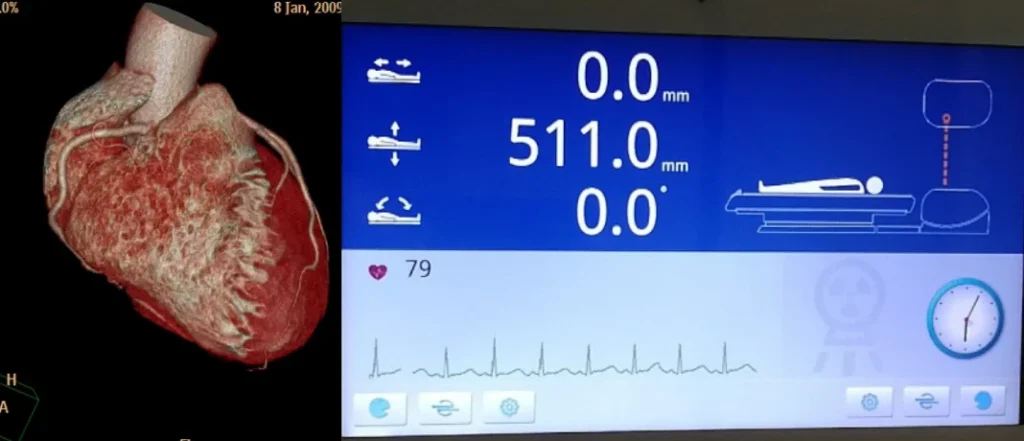

128-Zeilen-CT: Entwickelt für

Herzuntersuchungen

» Schneller 0,25-Sekunden-Herzscan

» EKG im Gantry integriert »

46 ms zeitliche Auflösung des Herzens »

Prospektive oder retrospektive Eingabe mit

bis zu vier Sektoren